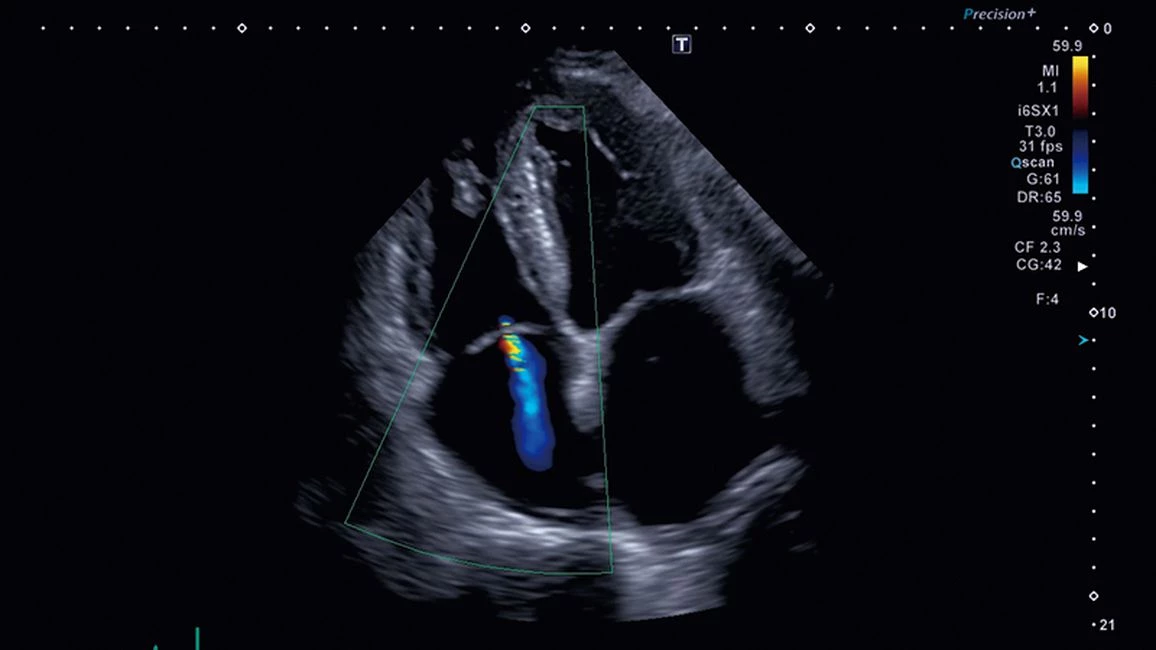

- Aortic Valve Analysis - инструмент анализа аортального клапана, обеспечивает измерения, полезные для хирурга при планировании транскатетерной имплантации аортального клапана

- 4D Mitral Valve Analysis - инструмент обеспечивает краткую анатомическую и функциональную оценку митрального клапана в 3D/4D. Мультипланарный вид предлагает удобный и четкий обзор различных плоскостей сканирования

- Кардиология,

- 3D/4D сердца: ✔

- Автоматические измерения в кардиологии - фракция выброса, объемы и пр. : ✔